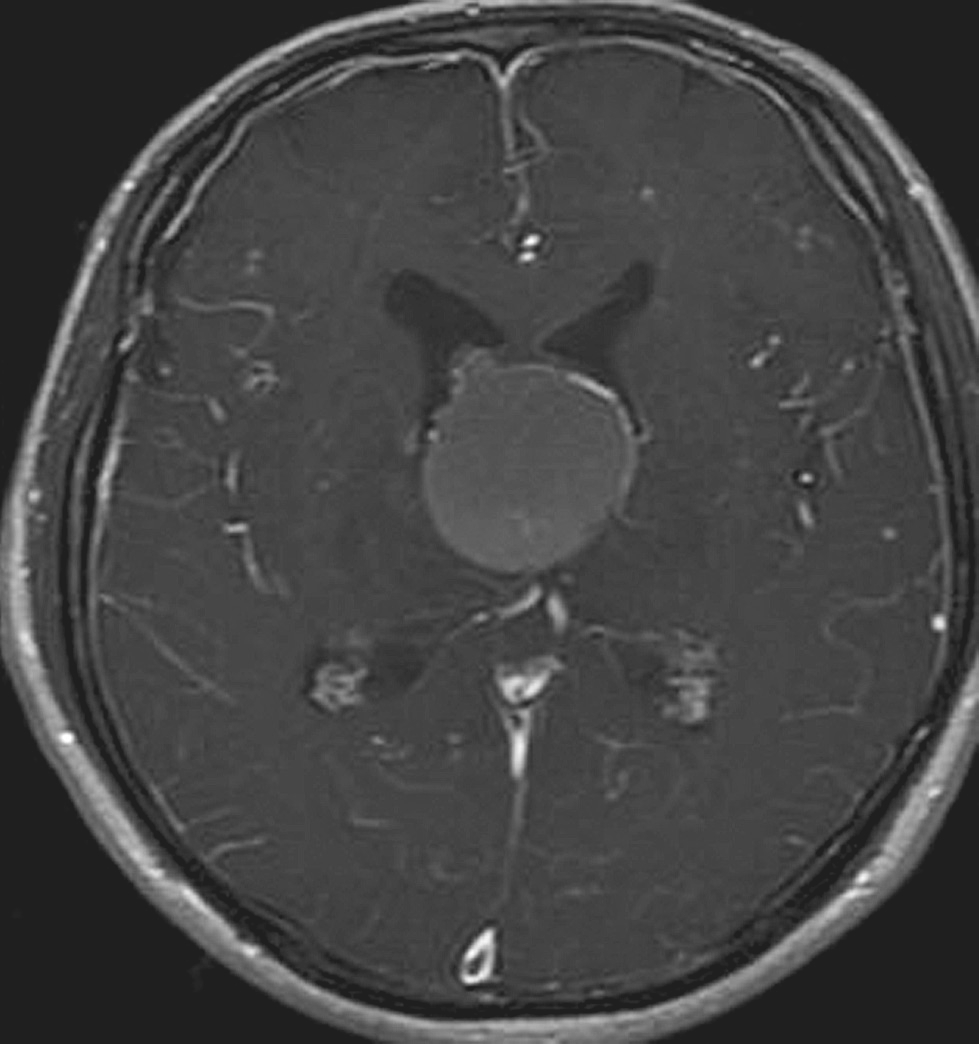

术后查体:神志恍惚,能简单回答问话。双瞳孔等大正圆,直径4.0mm,对光反射灵敏。颈软。四肢自主活动良好,肌张力略高。双侧Babinski征阴性。给予抗炎、脱水及对症治疗。术后24小时内复查头颅CT结果显示脑室系统明显变小(图5-1-4)。术后第3日患者神志清楚,问答合理。双侧脑室引流管通畅。术后第4日完善头颅MRI检查(图5-1-5)。双侧侧脑室外引流术后第6日于全身麻醉下行“经纵裂-胼胝体-穹窿间入路第三脑室内占位病变切除术”。手术过程顺利,复查头颅CT显示完全切除肿瘤,脑室大小基本正常(图5-1-6)。病理检查结果回报:胶样囊肿。患者2周后出院。目前随访恢复良好,未见肿瘤和脑积水复发。

图5-1-5 脑室外引流术后MRI表现(引流术后第4日)